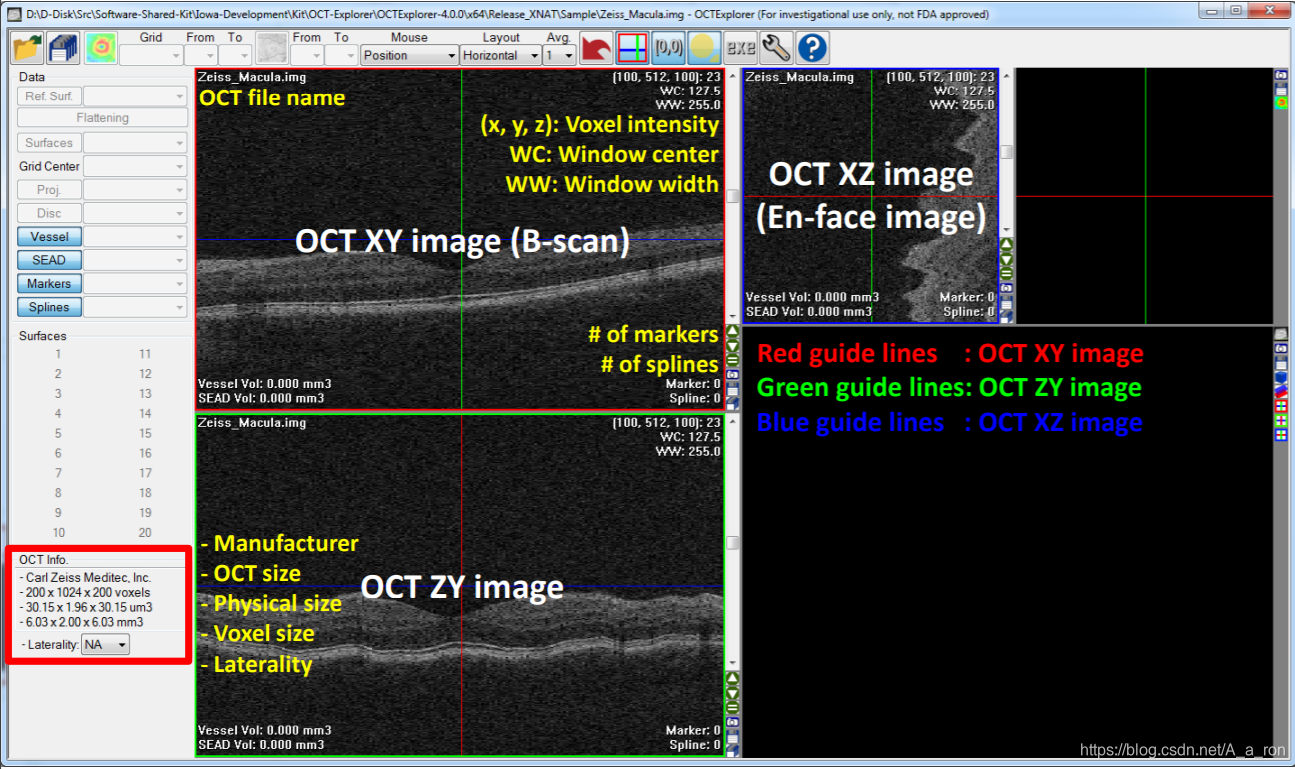

2. OCTExplorer

该软件由The Iowa Institute for Biomedical Imaging开发并维护,其包含了一系列的用于OCT影像处理的算法(目前仅支持windows平台)。软件持续得到更新,目前已经到了5.0.0版本。想要下载的话,只要同意相关的协议条款即可。同时,该软件也配置了较为详细的用户说明手册,对用户还是挺友好的。

2.1 软件界面示例

打开OCT图像: